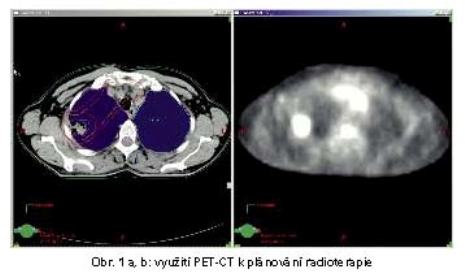

Pro určení GTV je velkým přínosem u NSCLC využití PET-CT. PET-CT zpřesňuje i stanovení stadia, u 20% pacientů detekcí vzdálených metastáz posunuje klasifikaci do stadia IV. Je signifikantně přesnější pro průkaz metastaticky postižených uzlin v mediastinu než CT. Senzitivita PET v porovnání s CT je 0,79 vs 0,60 a specificita je 0,91 vs 0,77. PET-CT umožňuje redukci GTV u 15-30% pacientů a naopak brání opominutí postižených mediastinálních uzlin u 10-25% pacientů (obr. 1). Výrazně snižuje variabilitu zakreslení GTV různými lékaři.